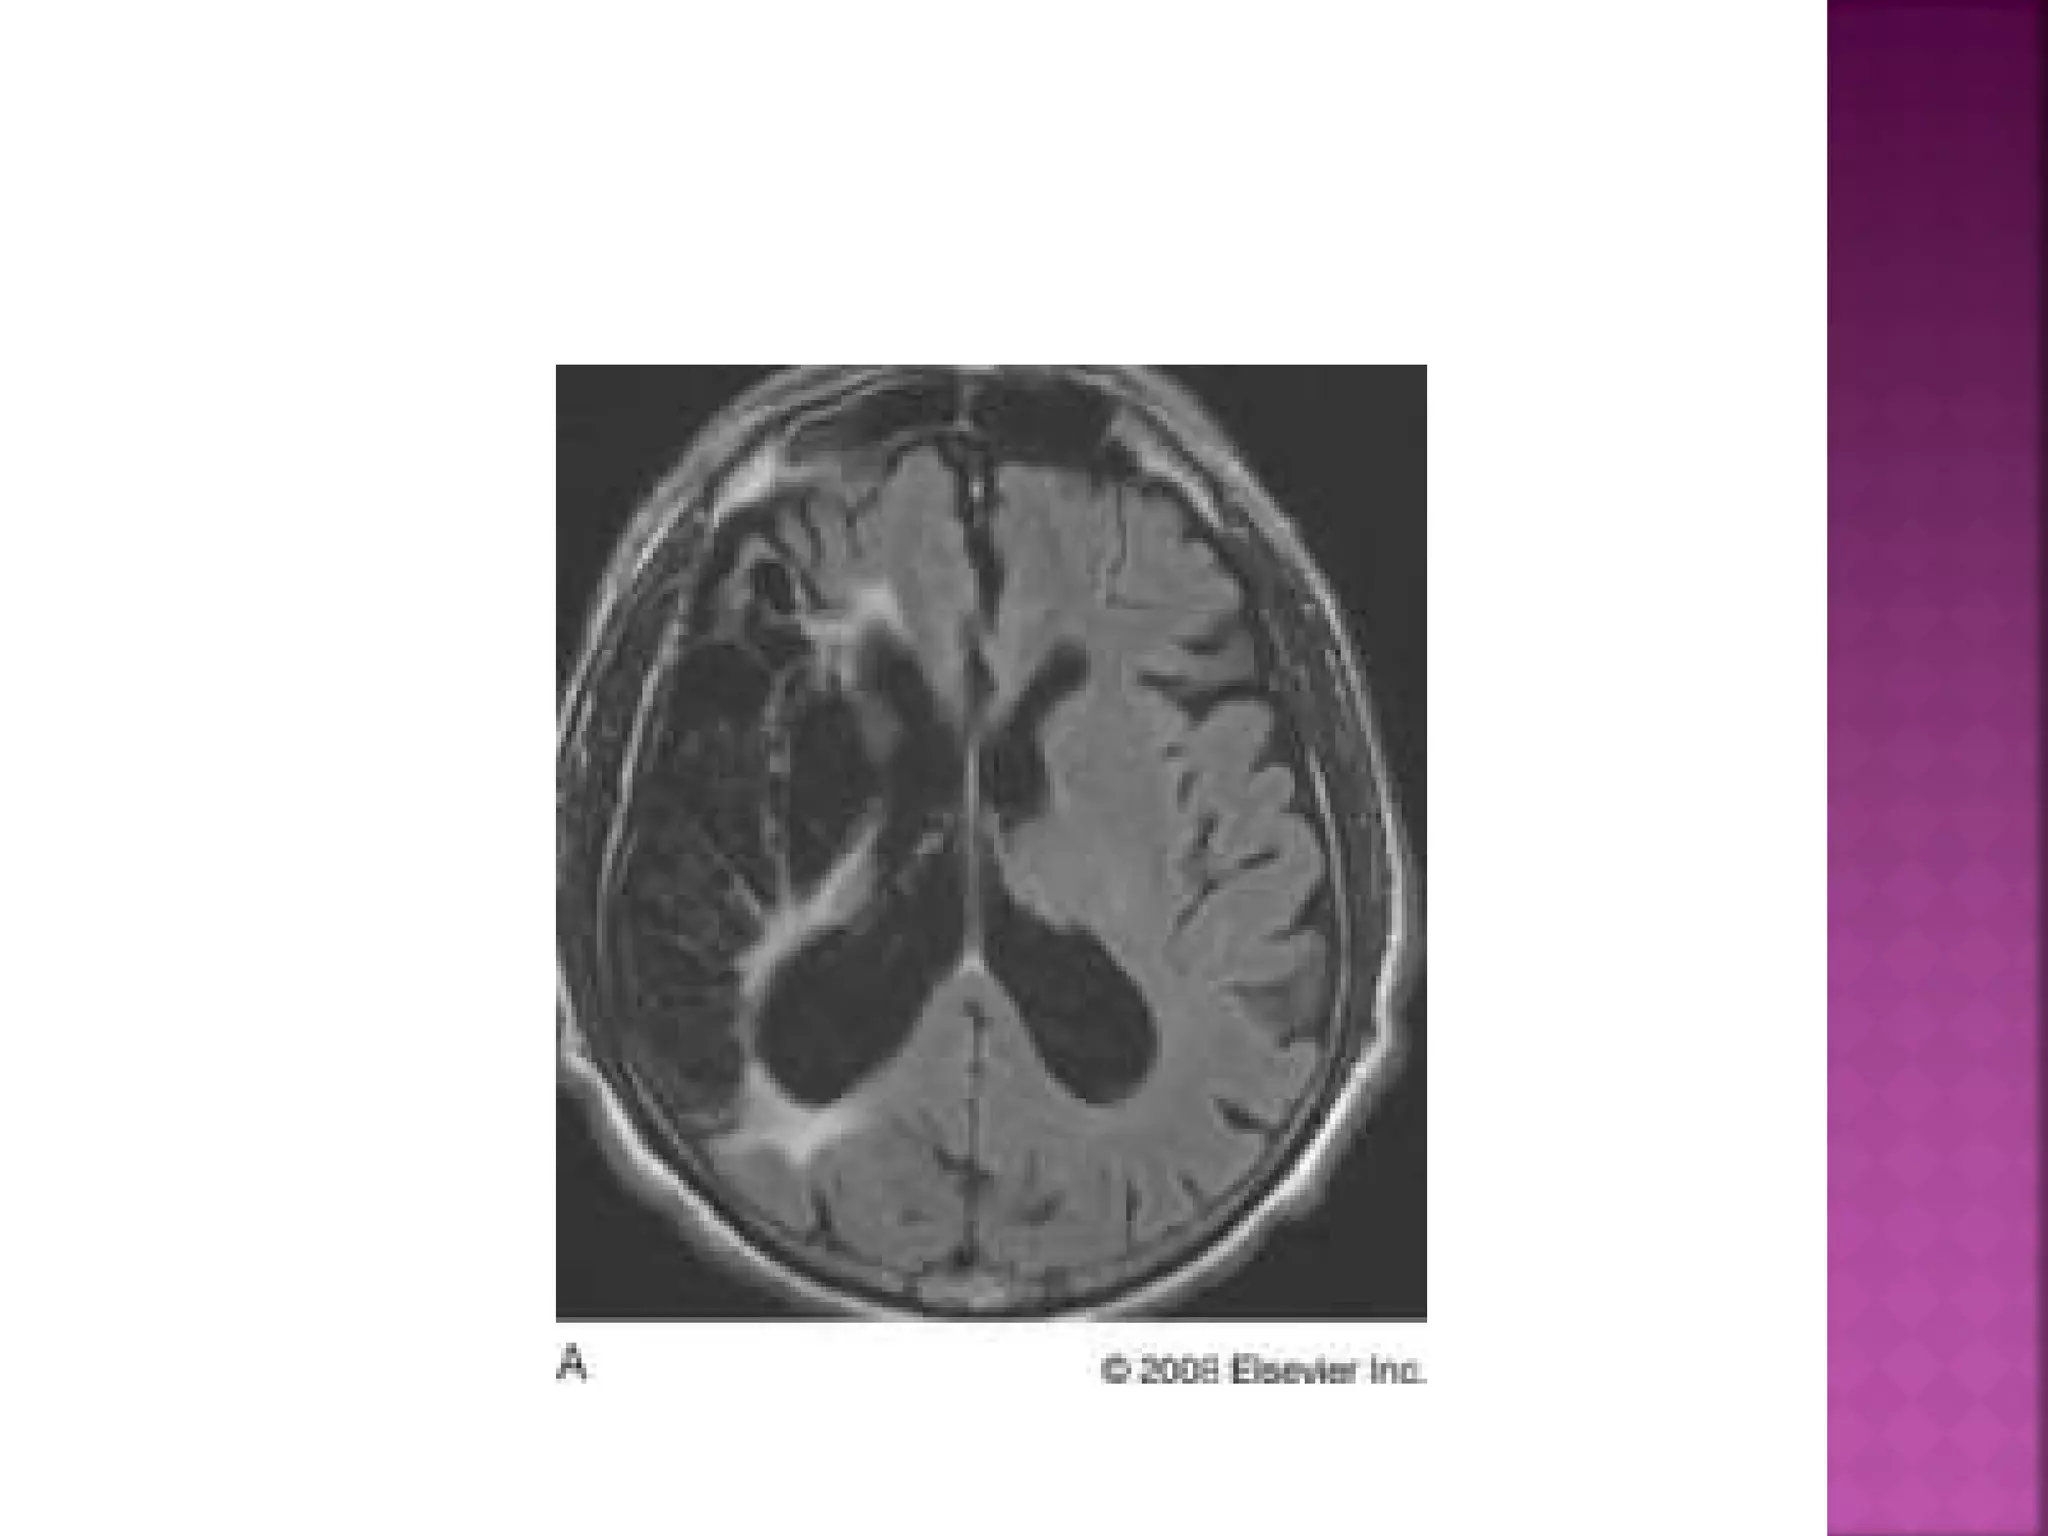

 On T2WI andFLAIR infarction is seen as high SI. These sequences detect 80% of infarctions before 24 hours. They may be negative up to 2-4 hours postictus!

• 21.

 High signal onconventional MR-sequences is comparable to hypodensity on CT. It is the result of irreversible injury with cell death. So hyperintensity means BAD news: dead brain.